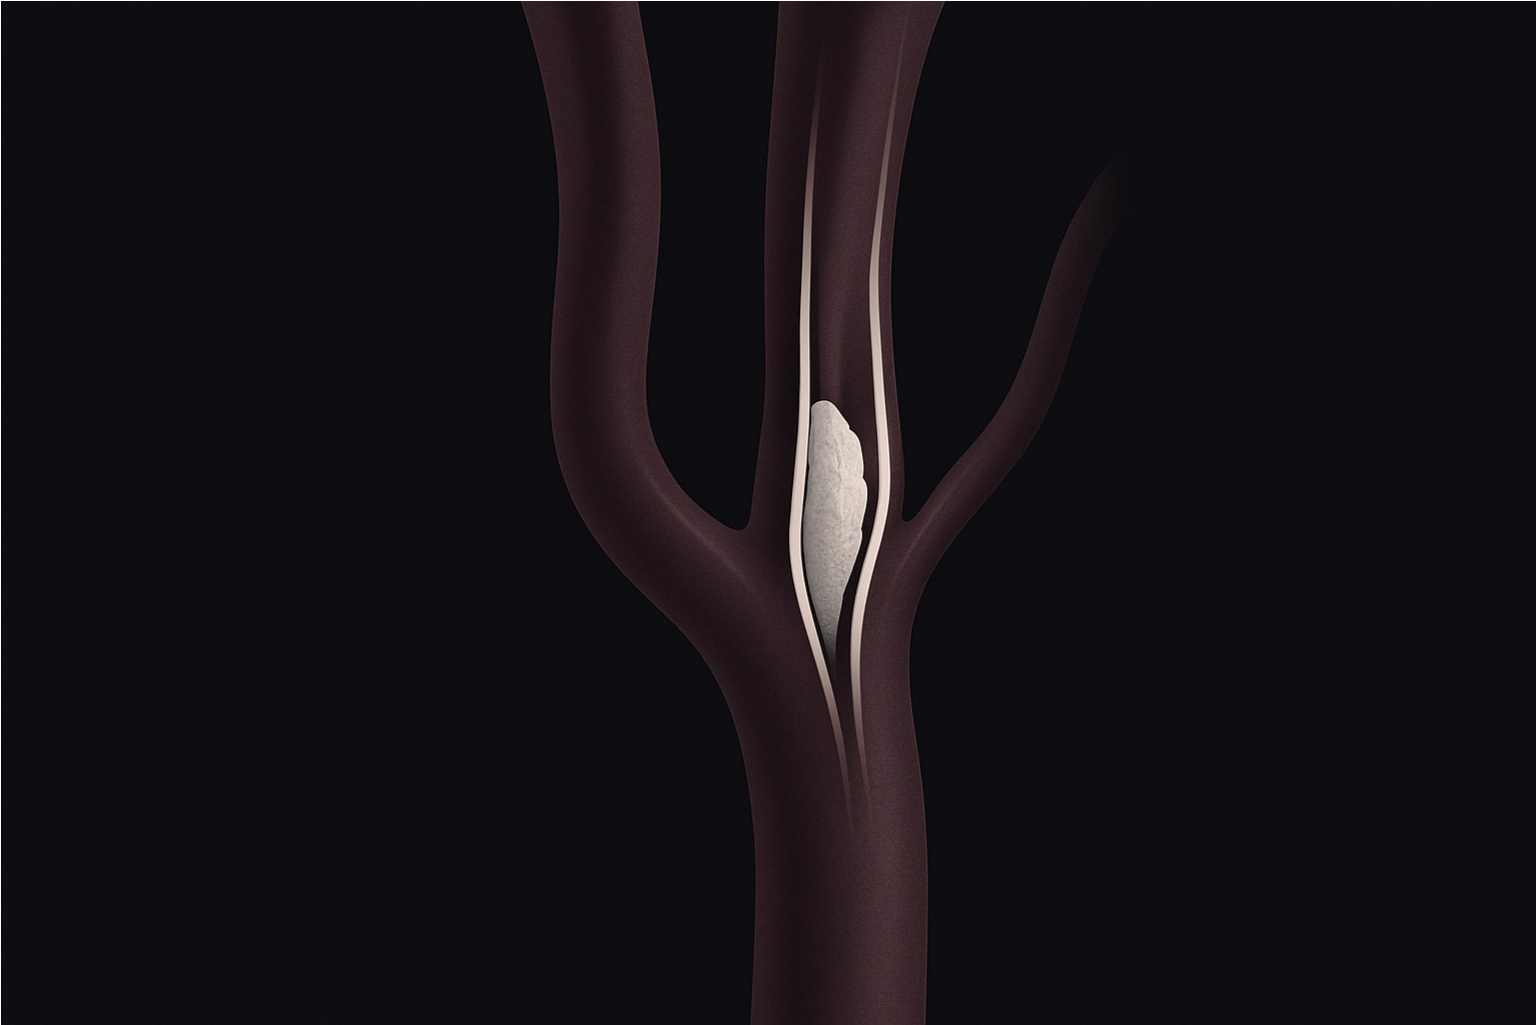

O que é a estenose de carótida?

As artérias carótidas ficam no pescoço e levam sangue ao cérebro. Quando essas artérias sofrem um estreitamento (estenose), geralmente por acúmulo de placas de gordura (aterosclerose), há risco de reduzir o fluxo sanguíneo ou até soltar fragmentos da placa, que podem entupir vasos cerebrais e causar derrame (AVC).

2. Cirurgia de endarterectomia de carótida

- É o tratamento clássico e mais consolidado.

- O cirurgião faz uma incisão no pescoço, abre a artéria e retira a placa de gordura que está obstruindo o fluxo.

- A artéria é fechada e o sangue volta a circular livremente.

- Tem ótimos resultados em casos de estenose grave, principalmente em pacientes sintomáticos.